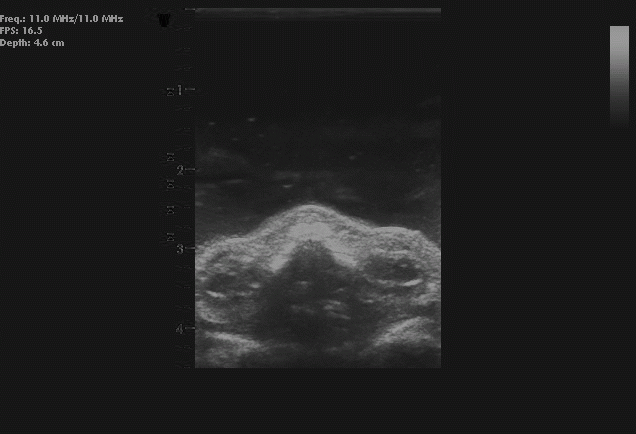

P.S.: V prilohe je nahlad na "rez"

FACET302_exposure.png

Obrazky niesu z CT, ale z ultrazvuku. A to je asi cely problem. Vsetky medicinsky zamerane programy dokazu spracovat CT obraz, alebo magneticku rezonanciu. Ked chcem otvorit tieto obrazky z ultrazvuku, programy bezpecne zamrznu. Asi je ten DICOM nie uplne rovnaky. A slicer tiez zlyhal.

Z rozmazaných černobílých snímků bude určitě mizerný výsledek. Rozhodující pro kvalitu tisku je ostrý přechod mezi černou (polymer neztuhne) a bílou - světlem (polymer vytvrdne). Navíc je potřeba tisknout kolem vrstvy 0,05 mm. To znamená mít snímky po 0,05 mm a musely by být centrované a na stejném místě. Netuším, jestli ultrazvuk je něčeho takového schopen.